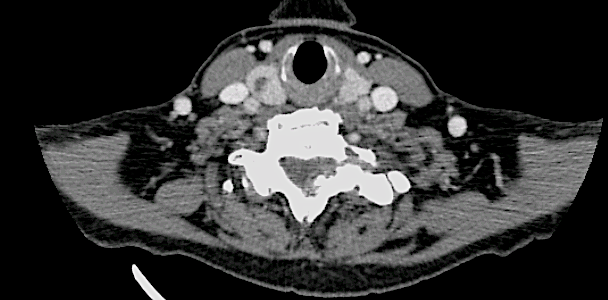

Se solicitó un TC observando signos de espondilosis avanzada C5-C6-C7 y ausencia de infiltración ósea.

En la imagen coronal se aprecia relación íntima de la lesión con la faceta C7-Th1 que nos hizo sospechar el diagnóstic